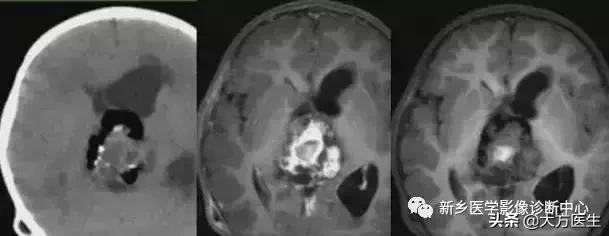

18、松果体区肿瘤

此区肿瘤为生殖细胞瘤,松果体瘤,畸胎瘤。

左1为松果体区畸胎瘤,右2为松果体细胞瘤

19、畸胎瘤

为胚胎残存肿瘤,常位于中线部位,含有脂肪、钙化、及等密度影,增强多为不均匀强化。